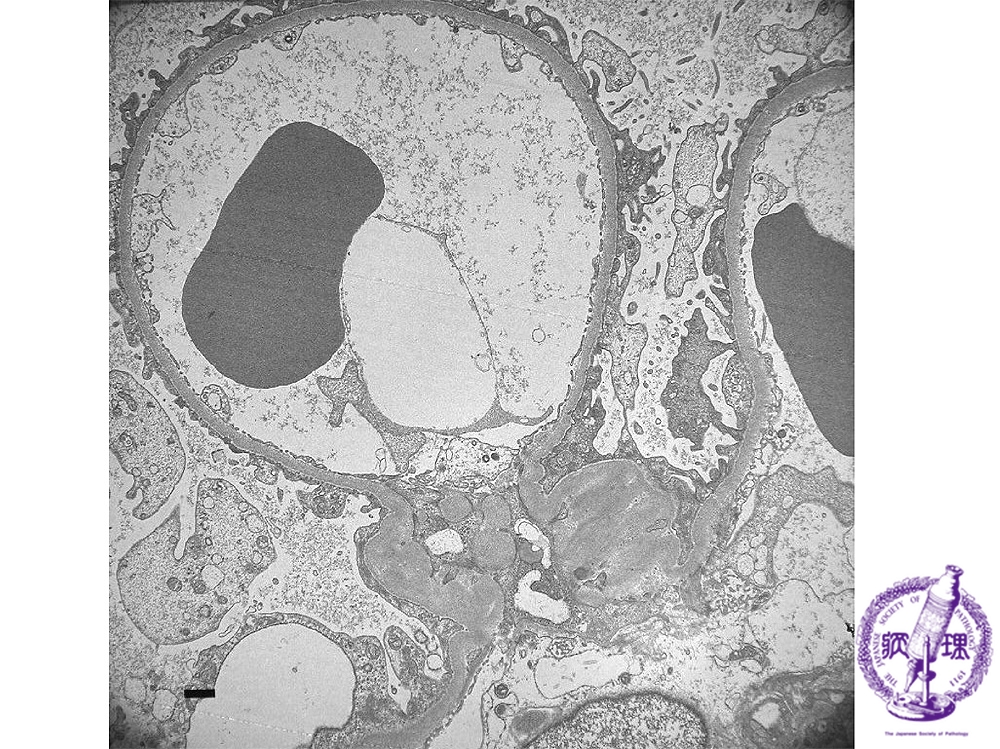

- (1)Minimal change disease

Electron microscopic findings: The pedicles of glomerular podocytes show fusion (red arrow).